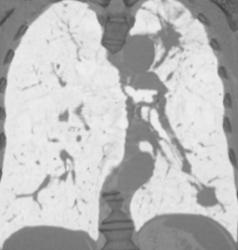

Chest Wall Collaterals Due to Vascular Obstruction